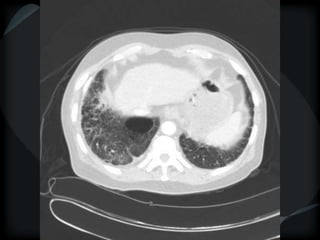

Septal Pattern – lymphatic/venous

 Secondary lobule outlined- interlobular septum

● Smooth – pulmonary veno-occlusive disease, mitral

stenosis, capillary hemangiomatosis, LC

● Beaded – lymphangitic carcinomatosis, lymphoma,

lymphangiomatosis, sarcoid

Rare = non-Langerhans’ cell histiocytosis (bone+pleura)

amyloidosis

PHTN – PA 39mm

39.2mm

PHTN and septal thickening

? PVOD